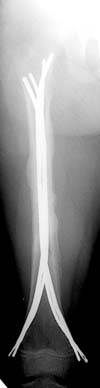

Date: Wed, 20 Jun 2001 23:19:13 -0700

From: Carlo Bellabarba

alex,

here's a recent Ender example with three-month followup. sorry about the

quality of the injury image--there were better outside films that have since

disappeared. I still think this technique is useful, even in rotationally

unstable patterns such as this one. i take the nails out at 6 mos, and leave

them a little proud on purpose (this 10 year-old is a bit of chunkster so

they don't bother him) and suture them down so that they don't back out

more.

it aren't fancy, but it's quick and seems to work.

carlo bellabarba